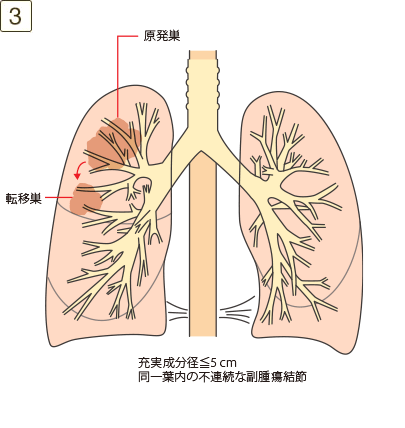

T3

充実成分径>5cmでかつ≦7cm、または充実成分径≦5cmでも以下のいずれかであるもの・壁側胸膜、胸壁(superior sulcus tumor を含む)、横隔神経、心膜のいずれかに直接浸潤・同一葉内の不連続な副腫瘍結節